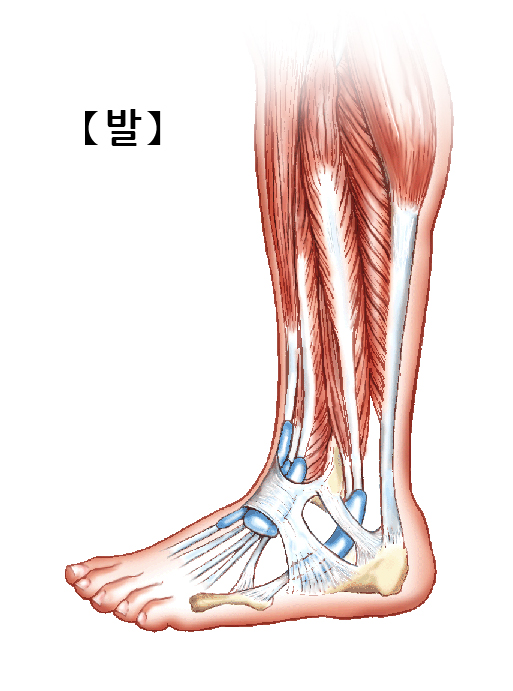

발은 뼈, 근육, 힘줄, 관절, 인대, 신경, 혈관들로 구성되어 있습니다.

근육과 힘줄

발은 총 19개의 근육과 힘줄을 가지고 있습니다. 다리와 발 동작은 전면근육, 측면근육, 후측표면근육, 후측심부근육의 운동에 의해 주로 이루어지게 됩니다. 힘줄은 뼈와 근육을 연결하는 부분입니다. 발에는 우리 몸 중에서 가장 큰 힘줄인 아킬레스건이 위치하고 있는데, 이는 이동에 중요한 역할을 담당합니다.

관절

인대

발에는 107개의 인대가 존재합니다. 인대는 관절을 둘러싼 탄성조직으로 관절이 움직일때 뼈의 위치를 유지시켜주고 결합시켜줍니다.